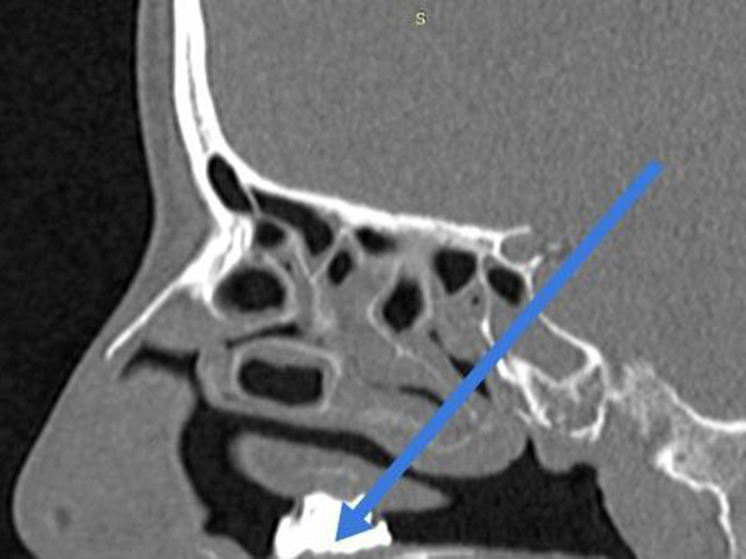

Врачи обследовали пациентку и обнаружили в носовой полости инородное тело. Потребовалась госпитализация и вмешательство хирургов. Во время операции специалисты по частям извлекли из носа женщины …уголь, застрявший в грибковых наростах.

Судя по крепости частиц, можно подозревать, что это каменный уголь. Пациентка сообщила врачам, что не помнит, как он оказался в ее носу. Возможно, она пыталась лечить насморк народными методами, но не смогла предугадать опасные последствия.